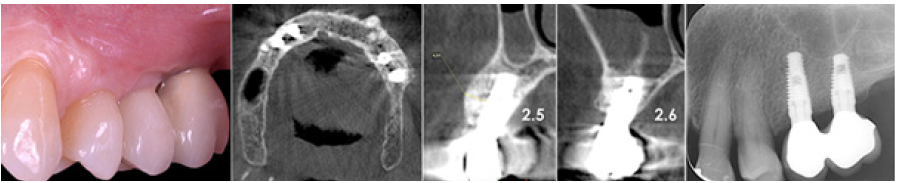

The patient was a woman 64-year-old with history of periodontal disease. Non-smoker, in good general health, she did not report allergies or intolerances to anesthetics and drugs. She presented with stage IV periodontitis and partial edentulism in the second quadrant with a horizontal bony deficiency. The first step represented full-mouth disinfection and systemic therapy with Metronidazole and Amoxicillin for 7 days to reduce the infection. After 3 months of good periodontal maintenance, the CBCT showed a defect where the thickness of the residual bone was less than 5mm. The thickness of the buccal plate prior to surgery was less than 1mm while minimum thickness recommended from evidence should be 2mm [19]. After local anesthesia with 4% Articaine with adrenaline 1:200,000, a crestal incision and a full-thickness vestibular flap with vertical incisions mesial to tooth 24 and distal at tuber level was elevated. A full-thickness palatal flap was also raised 10mm apically without vertical incisions. After obtaining adequate passivation of the buccal flap, decortications of the buccal bone wall were performed using the IM1S PiezoSurgery insert (Mectron, Carasco, Italy). IK 3.8x13mm and IK 3.8x11mm implants (Resista Group, Verbania, Italy) were placed in the sites 25 and 26. There were’t exposed threads, but the buccal bone wall was thin.

The surgery ended with 5/0 Polypropylene horizontal mattress sutures (Aragò, Barcelona, Spain). Amoxicillin 500mg every 8 hours for 7 days, Ibuprofen 600mgx3 for 3 days, Chlorhexidine 0.20% rinses morning and evening for 7 days were prescribed as postoperative medication. Postsurgical CBCT demonstrates a buccal augmentation of 4.05mm. The sutures were removed after 2 weeks of uneventful post-operative course (Figure 1-7). Six months after surgery, the clinical aspect showed an excellent volume of convex shape and hard consistency. The CBCT highlighted a horizontal gain of 4.05mm with initial mineralization. The day of re-entry the area displayed a new anatomy. The mesial implant was covered with hard tissue reproducing the shape of the cover-screw. A biopsy was taken and stored in 10% buffered neutral formalin and sent for histological examination. Healing abutments were connected and soft tissue sutured in place. After 3 months a prosthetic restoration was performed by means of a gold-ceramic screwed bridge. The histological result showed newly formed trabecular bone, in close contact with residual particles and osteoid matrix where newly formed blood vessels and active osteoblasts were present. There were not inflammatory or necrotic cells. Three years after surgery, the clinical and CBCT control show hard and soft tissue stability. The horizontal measurement of new vestibular bone is stable at 4.05mm. The peri-apical rx shows no marginal bone loss. Four years after surgery, a significant finding was observed on the new CBCT: the graft appeared almost totally reabsorbed in favor of new bone which has a radiological quality similar to that of the native bone and there is a new mature cortical plate [21] similar to the palatal native bone (Figure 8-15).

Figure 1: Initial status. Buccal plate concavity on the upper left quadrant.

Figure 2: The thickness of the bone was less than 5mm. The buccal bone wall at planned implant position was less than1mm thick.

Figure 7: Post-operative CBCT.